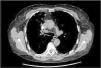

Pulmonary embolism due to vertebroplasty material: Another possible complication of severe asthmatics

Embolia pulmonar por material de vertebroplastia: otra posible complicación de los asmáticos graves